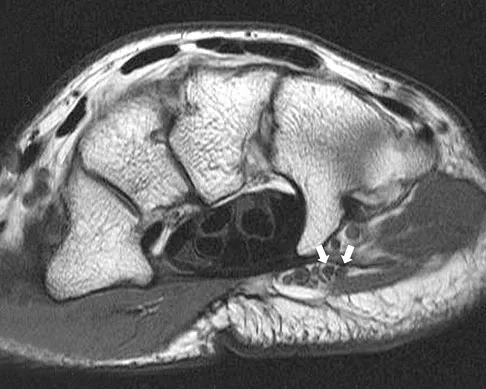

A 39-year-old competitive cyclist sustains an injury to her left hip in a fall. Gadolinium arthrography, with an accompanying MRI scan, is shown in Figure 31. A cleft, or defect, identified by the arrow, indicates a detachment of the

Explanation